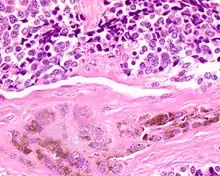

| A bone resection sample showing the pigmentation below the surface in a melanotic neuroectodermal tumor of infancy | |

The tumor is usually very well circumscribed but not encapsulated. There are two cell types present (biphasic), arranged in alveolar or tubular configurations.

There are centrally located, small, darkly staining cells comprising the majority of cells. These cells have a fibrillary cytoplasm surrounding round nuclei with coarse and heavy nuclear chromatin. These cells are surrounded by much larger polygonal cells that have open nuclear chromatin and abundant opaque cytoplasm that has granular melanin pigment.

There is usually no hemorrhage, necrosis or increased mitoses.[1][4]